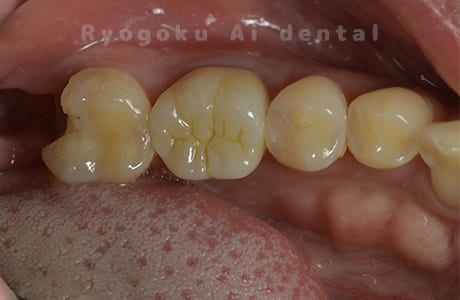

Case11

-

- 原因

- インレー2次カリエス、ならびにインレー脱離

- 治療内容

- セラミッククラウン、セラミックインレー

- 治療費用

- 123,000円×2(セラミッククラン)、77,000円(セラミックインレー)

銀歯が取れて、ご来院された患者様です。奥歯2本をセラミッククラウン、手前の小臼歯をセラミックインレーで治療を行いました。